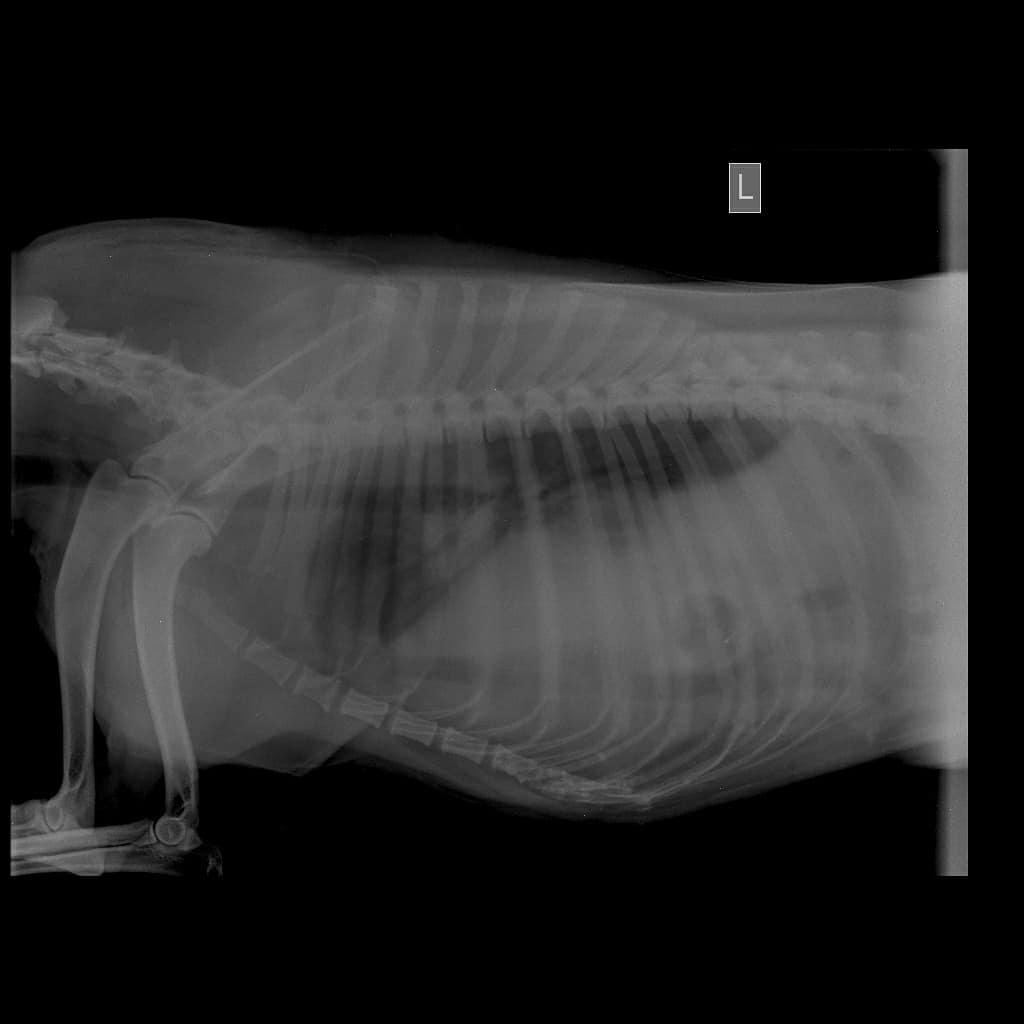

Took her back to the clinic in the evening for x-rays.

The x-rays reveal she has *DIAPHRAGMATIC HERNIA*

A diaphragmatic hernia is a condition in which a break in the diaphragm allows abdominal organs to move into the chest. In dogs, being hit by a car is a common cause of diaphragmatic hernia.